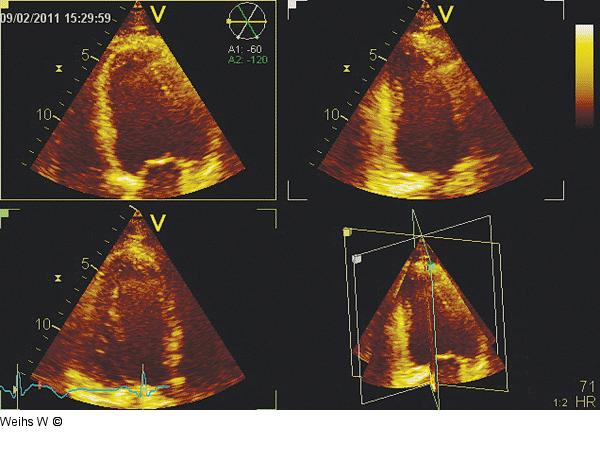

Abbildung 4: Apikale Schnitte Triplane Darstellung der "klassischen" apikalen Schnitte in einem Herzzyklus. Die Infarktausdehnung erstreckt sich über die basalen plus mittleren inferioren bis zu den anterolateralen Segmenten. |

Triplane Darstellung der "klassischen" apikalen Schnitte in einem Herzzyklus. Die Infarktausdehnung erstreckt sich über die basalen plus mittleren inferioren bis zu den anterolateralen Segmenten. |